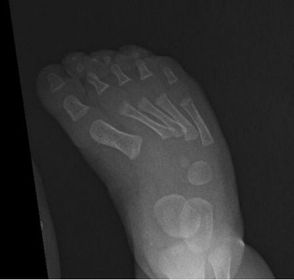

| Describe the alignment of metatarsal 2 | There is no angulation nor displacement of the distal segment relative to the proximal segment. |

| Describe the alignment of metatarsal 3 | The distal segment is displaced laterally (50% apposition) and angulated medially. |

| Describe the alignment of metatarsal 4 | The distal segment is displaced laterally (75% apposition) but there is no apparent angulation. |

| Describe the tubulation of the metatarsals | Metatarsals are overtubulated - decreased girth. |

| Describe the tubulation of the metatarsals | Metatarsals are undertubulated - increased girth. |